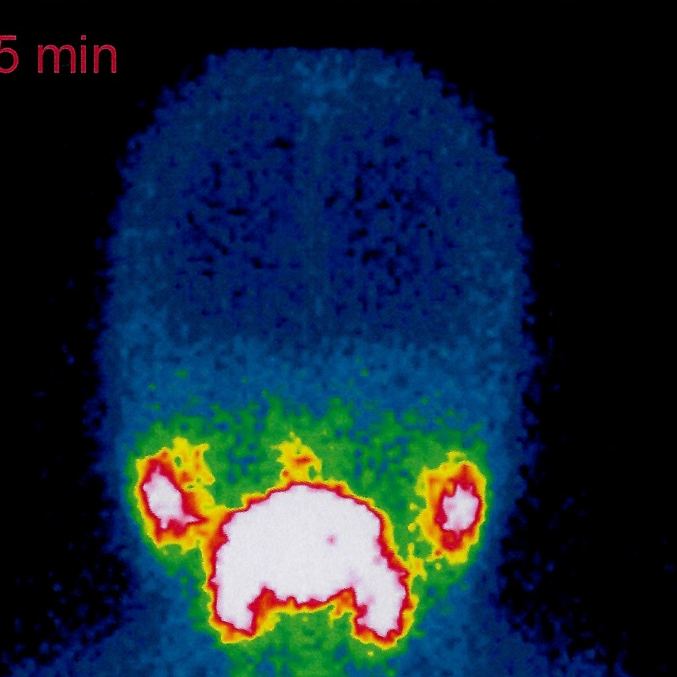

La exploración consiste en la inyección intravenosa de un radiofármaco y posteriormente se obtienen imágenes bajo cámara a las 20 minutos de la inyección.

Identificación de lesiones tumorales o metastásicas en tejido cerebral.